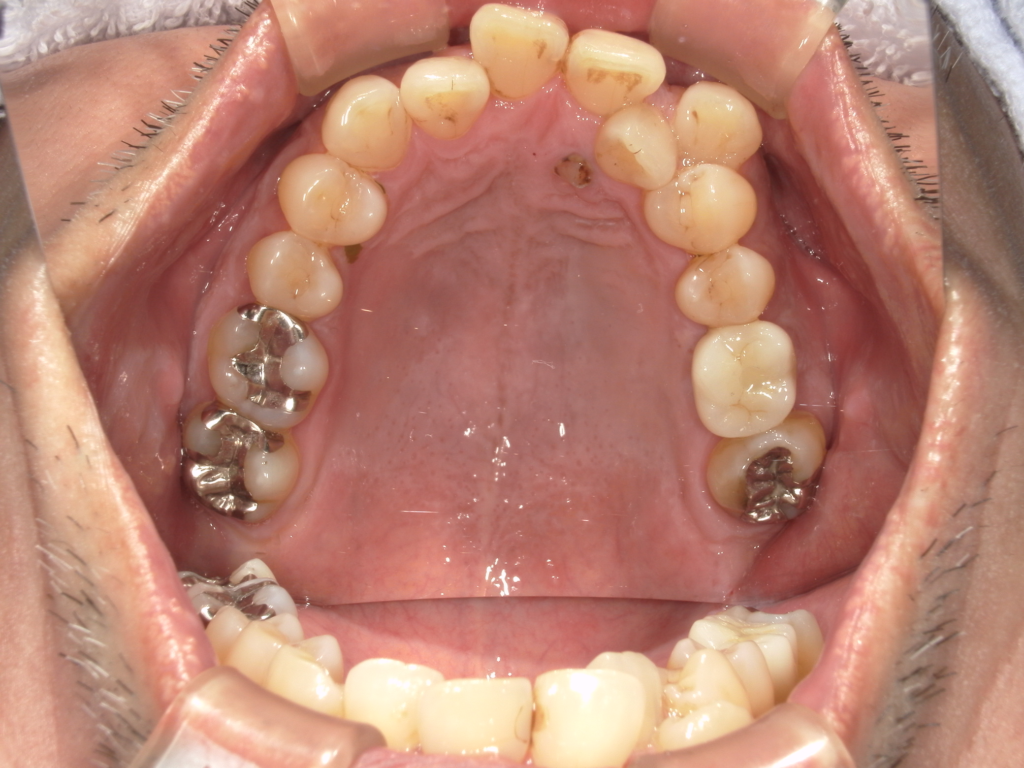

前歯の4本が、残すのが難しい状況となり、インプラント治療を行いました。

インプラントは前歯に2本埋入し、4本の前歯を作っています。歯を抜くと同時にインプラントを埋入し、仮歯を作りました。その後2ヶ月で、被せ物を入れました。被せ物は、セラミックスで作っています。

治療前

治療後